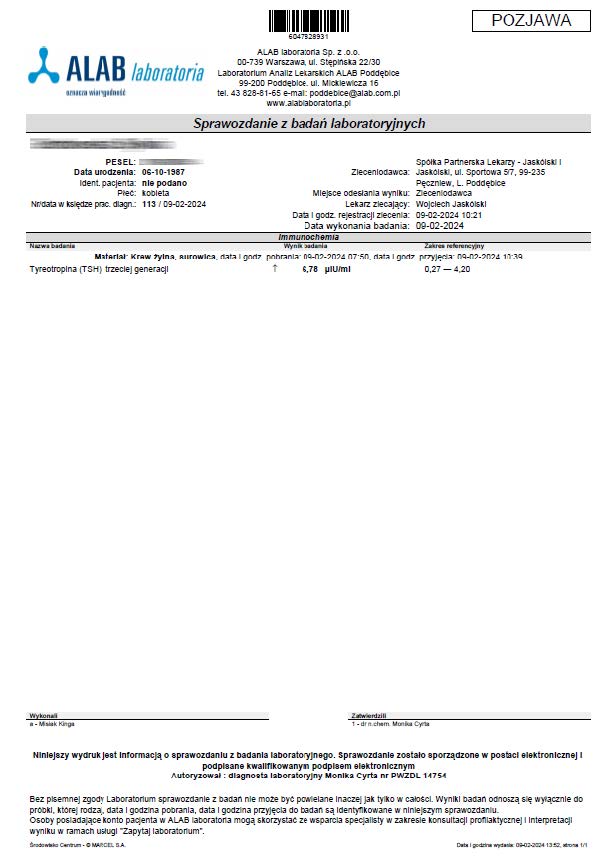

PRZYKŁAD EFEKTU PREPARATU NA NIEDOCZYNNOŚĆ TARCZYCY

Kobieta lat 59 z niedoczynnoscią tarczycy, bez przyjmowania lewotyroksyny. Kobieta przyjmowała preparat przez okres ponad 3 miesięcy. Przy zachowaniu naturalnego cyklu komórkowego i stałemu stymulowaniu mitochondriów osiągneła następujące wyniki kuracji:

Po zaobserwowaniu znacznej poprawy w ogólnym samopoczuciu, kobieta postanowiła wykonywać badania ze zwiększoną częstotliwością oraz kontrolę prób wątrobowych.

Po kolejnych dwóch miesiącach kobieta ponownie wykonała badania. Widoczne są: spadek TSH, obniżenie stanu zapalnego jak i spadek markeru wątrobowego GGTP.

Sukcesywnie co 2 miesiące można zaobserwować stały spadek parametrów zarówno wątroby jak i tarczycy. Kolejne badania potwierdzały dalszy spadek parametrów.

Po ponad roku kuracji badania wykazały dalszy postęp wycofania autoimmunologi tarczycy, potwierdzone również badaniem USG narządu.

Preparat wpływając na odbudowę mitochondriów zapewnił podłoże energetyczne do produkcji hormonów i odbudowy narządu. Brak ingerencji farmakologicznej wykazuje skuteczność nawet w podeszłym wieku, gdzie regeneracja jest wolniejsza a reakcje anaboliczne w znacznym stopniu spowolnione. Można zaobserwować także działanie ogólnoustrojowe obserwując spadek markeru wątroby, co jasno wykazuje poprawę funkcjonowania całego organizmu.

Kobieta lat 36 zastosowała terapię preparatem ze względu na pogarszające się samopoczucie i wysoki wynik TSH oraz anty-tpo jednoznacznie wskazujący na niedoczynność tarczycy. Brak zastosowanej farmakologii lewotyroksyną. Po zaledwie 12 dniach stosowania preparatu odnotowano znaczny spadek parametrów tarczycy oraz przeciwciał.

Wyniki odwrócenia procesów autoimmunologicznych wykraczają poza typowe leczenie i wykazują, że preparat wzmacnianjąc i stymulując mitochondria działa poprzez energetyczną optymalizację, co umożliwia długoterminową regenerację w różnych grupach wiekowych.